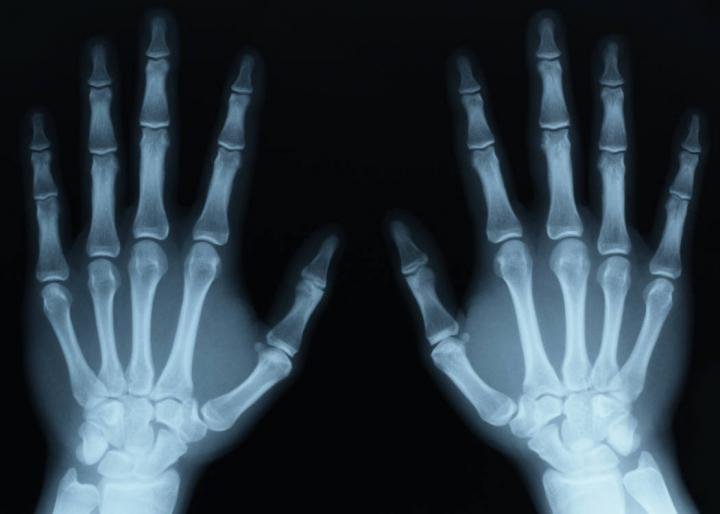

Broken-Bones-X-ray-personal-injury-claims-Scotland

How Much Compensation For Broken Bones?

If you feel you have a bone fracture, you should seek medical assistance immediately. A doctor will examine your injuries, typically using X-rays or other imaging techniques to determine if it is a simple fracture or a more serious break. Your medical records will be critical in determining your treatment strategy and any future bone fracture claims you may make.